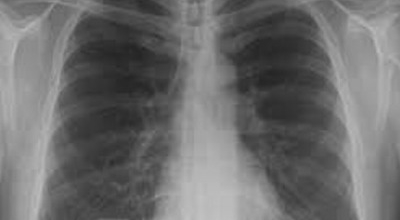

일반인이 근육통과 금이 간 경우의 차이는 거의 판별하기 힘들어요. 갈비뼈라고 하는 부분이 눈에 보이도록 붓는 것도 아니고, 멍이 들어서 아픈것도 아니기 때문이지요. 가장 정확하게 판별하는 방법은 엑스레이를 찍는 방법이지요.